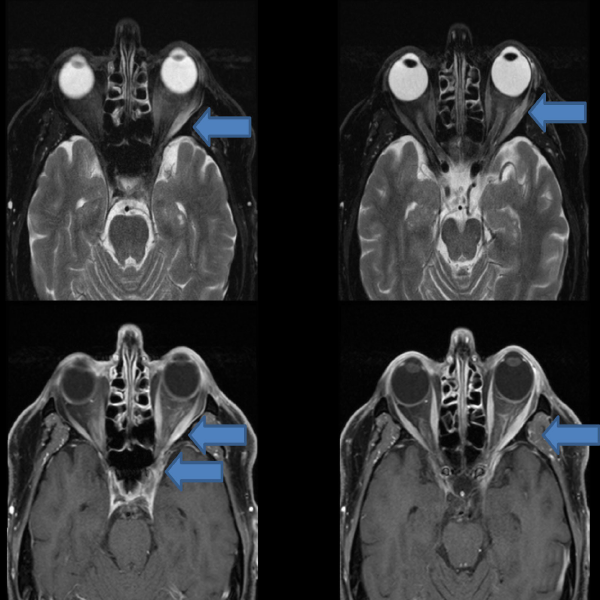

Ophthalmology Eponym of the Week: Tolosa-Hunt Syndrome refers to an extremely rare and painful ophthalmoplegia secondary to noninfectious inflammation of the cavernous sinus.

#ophthalmology #ophthotwitter #medtwitter